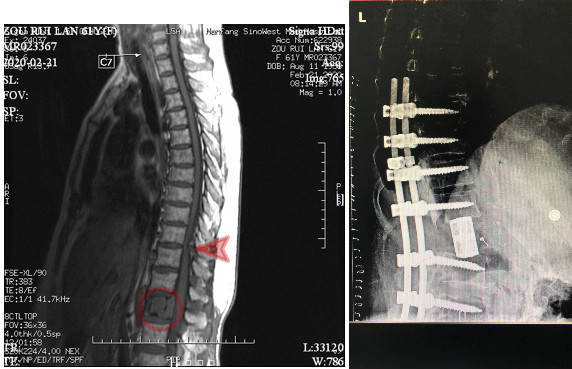

61岁的周阿姨(化姓)因突发排尿困难到医院检查发现腰椎肿物(怀疑恶性),转至广州求医。日前,在南方医科大学中西医结合医院接受了全脊椎整块切除术(TES)+胸椎板切除、椎管减压术,一次手..